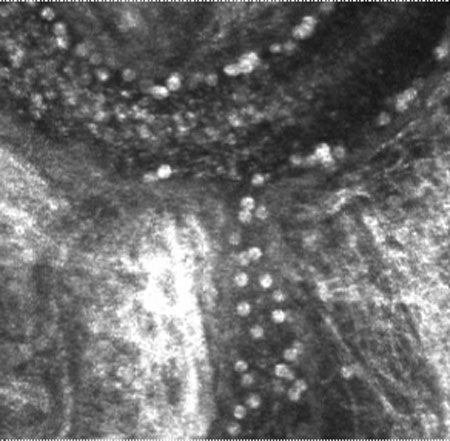

Figure 2.

Representative movie of rolling and arrested leukocytes in a patient with scleritis. Large numbers of rolling and arrested leukocytes are evident along the walls of the vessel.

Note that the slide bar at the bottom of the quicktime movie can be used to manually control the flow of the movie. If you are unable to view the movie, a representative frame is included below.